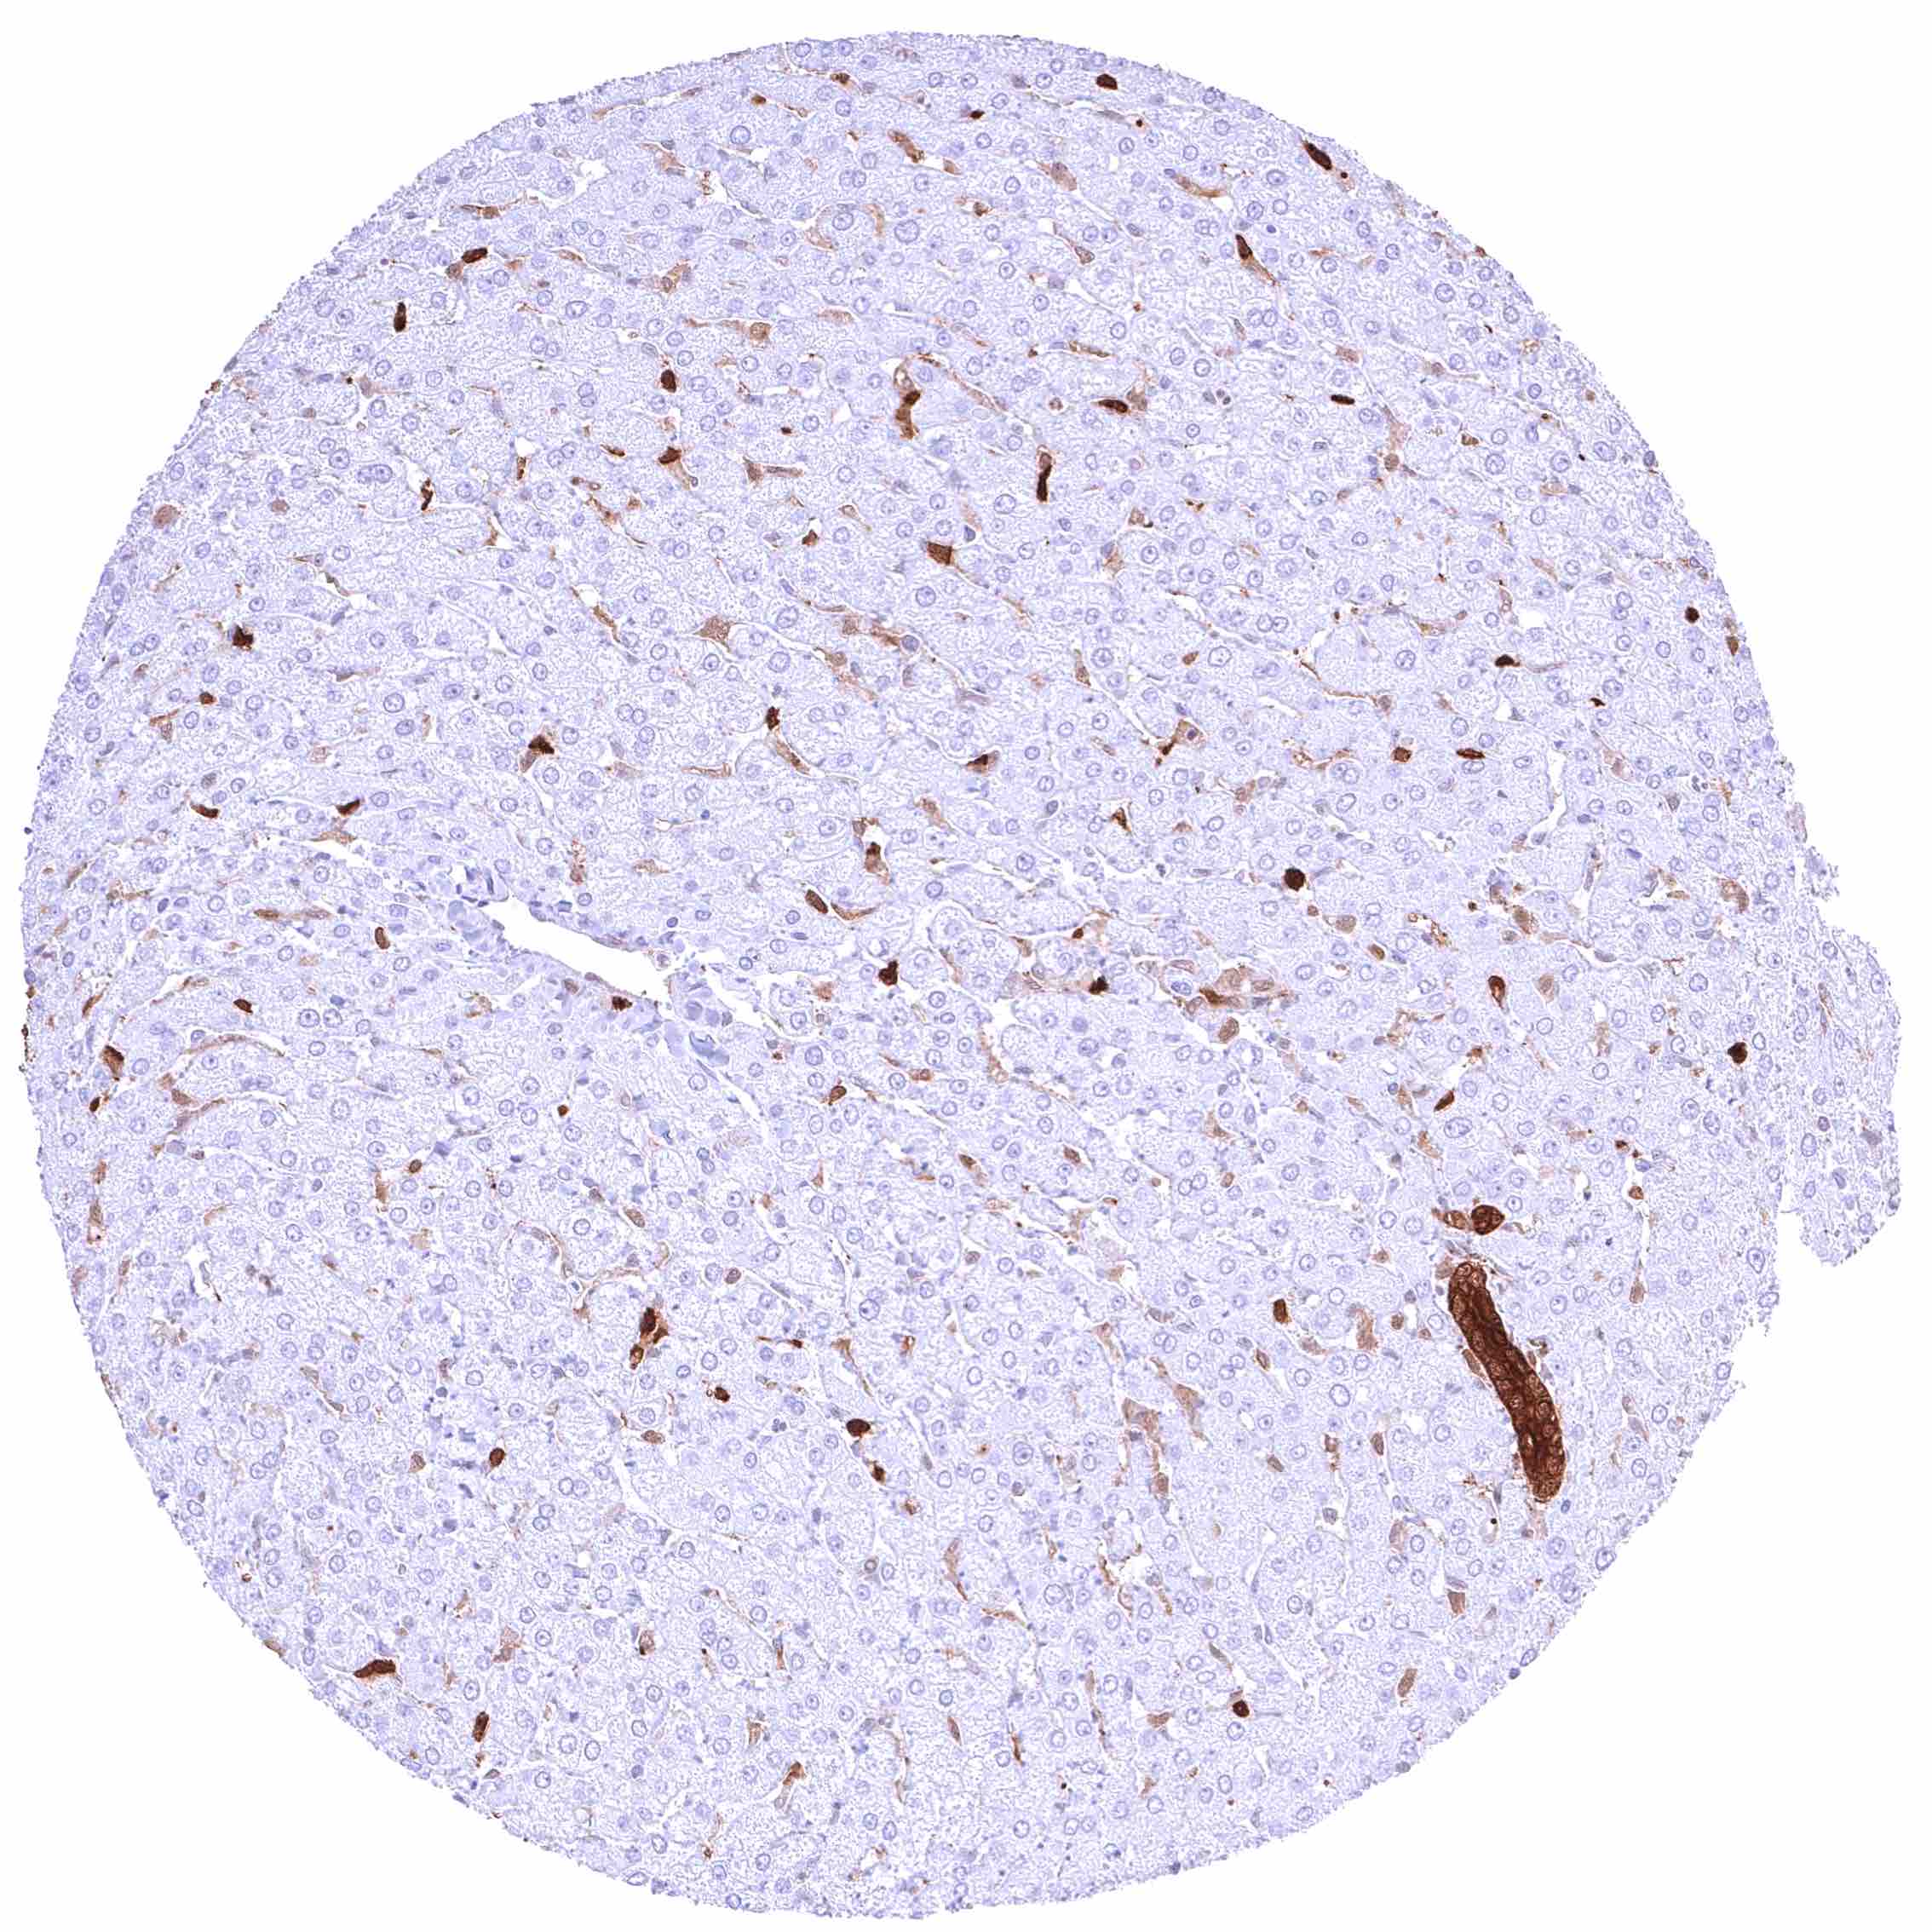

Liver – Weak to moderate, cytoplasmic GSTP1 positivity of sinus endothelial cells while staining is stronger in Kupffer cells. Hepatocytes are GSTP1 negative.